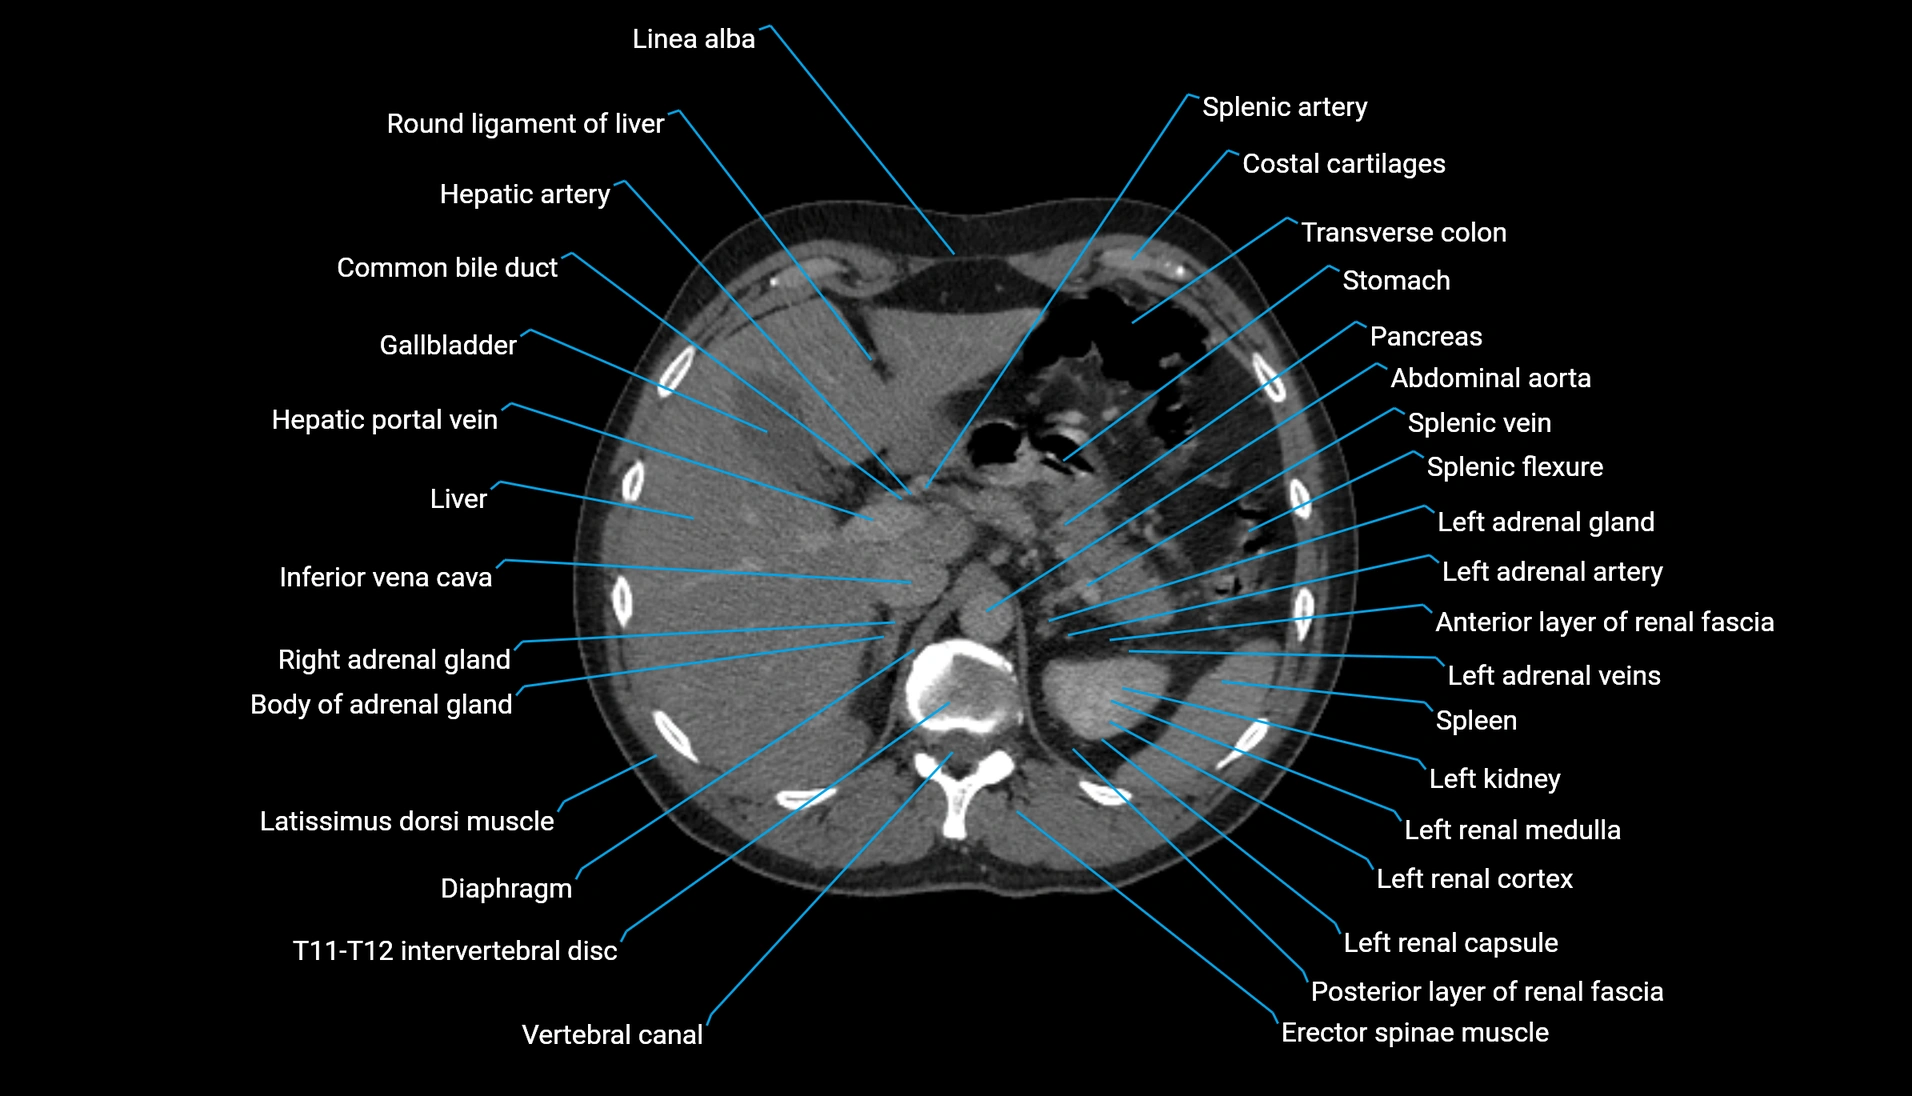

CT Appearance

Non-contrast CT:

-

Demonstrates cortical bone of acetabular rim in excellent detail

Detects fractures, dysplasia, retroversion, or bony overcoverage (pincer impingement)

3D reconstructions used in preoperative hip surgery planning

CT VRT 3D image

CT image